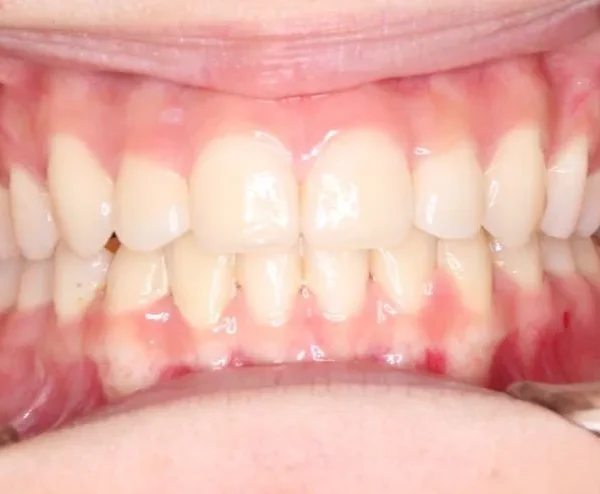

• 治療終了後

治療終了後

叢生は解消し、口元が大幅に引っ込み、下顎面高も縮小しました。

主訴が改善され、ご満足頂きました。